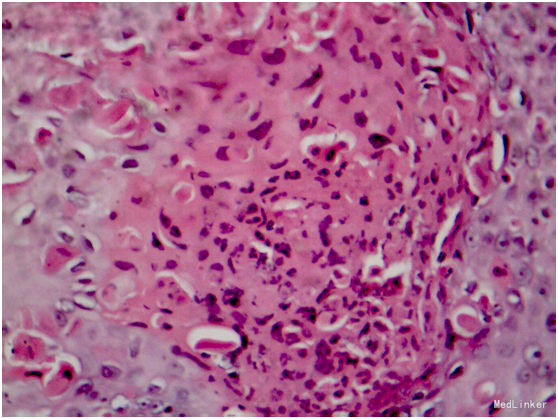

皮损:龟头、阴茎潮红,其上见数处浅表糜烂,龟头下方见一溃疡,周边一甲盖大小肿物,质较硬,有触痛。辅助检查:初步诊断:龟头溃疡、肿物查因:SCC?CA?其他?行肿物活检,病理:送检组织棘细胞排列紊乱,向真皮内不规则增生,可见角化不良细胞、异形细胞及不典型核分裂像。病理诊断:高分化鳞癌。

最后诊断:高分化鳞癌。 治疗:为尽量保证患者生活治疗,控制感染后行Mohs手术切除肿瘤。